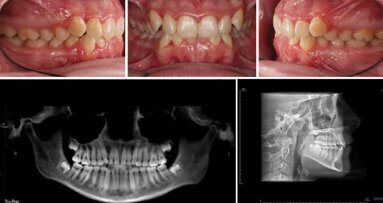

If the author has one suggestion, it is that orthodontists need to be aware that full evaluation of every orthodontic patient for TMJ disorder is mandatory. Every new patient should be evaluated for his or her TMJ status and should be questioned on the presence of key symptoms, such as headaches and ear and eye pain, as well as classic TMD intracapsular symptoms.

You will be asked at some time if the patient had the symptoms before orthodontic treatment; if you have no records, you have no defense. You will need to compare this with the records during and after the orthodontic treatment. Many orthodontists do this already, but it should be a universal practice.

- Identify any TMJ disorder signs and symptoms at the first consultation visit.

- Do a TMJ muscle and joint palpation on every new patient.

- Evaluate the TMJ risk assessment before commencing your orthodontic treatment plan.